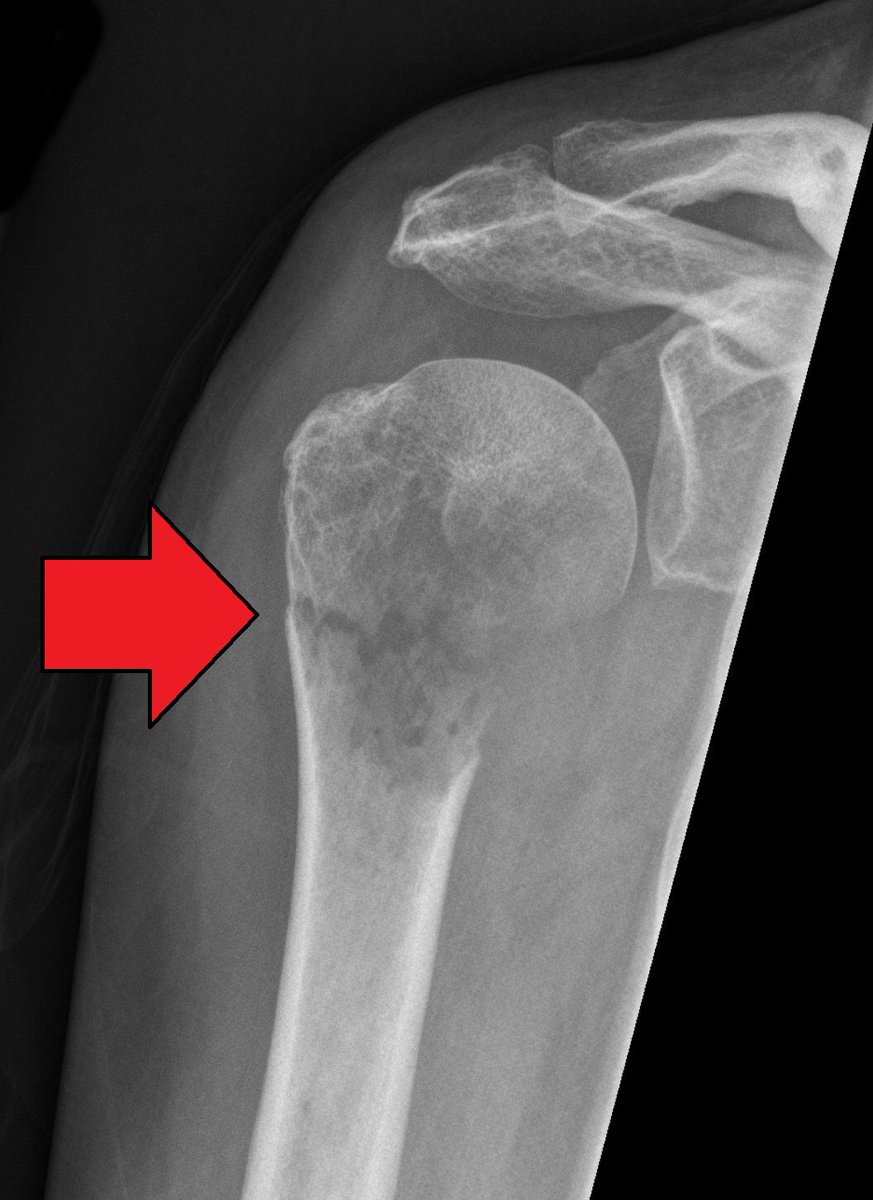

طيب حنّا ممكن نوضّح الكسر ونوصفه ونعرفه بعدّة اشياء :

Site

diaphyseal, metaphyseal, epiphyseal, intra-articular

موضّح لكم بالصوره .